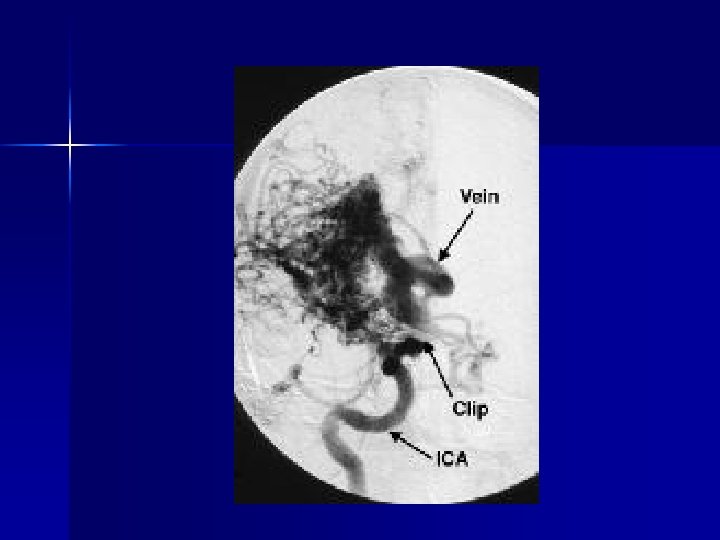

Subarachnoid Hemorrhage n n n n 1/10, 000 in U. S. Young, median age 50 50% mortality at 6 months 50% with initially normal exam, vitals, absence of neck stiffness Caused by anneurysm or AVM rupture Diagnosis: CT detects 93% in 24 hr, 80% after 24 hr Treatment: support ABCs, definitive treatment is coiling or clipping